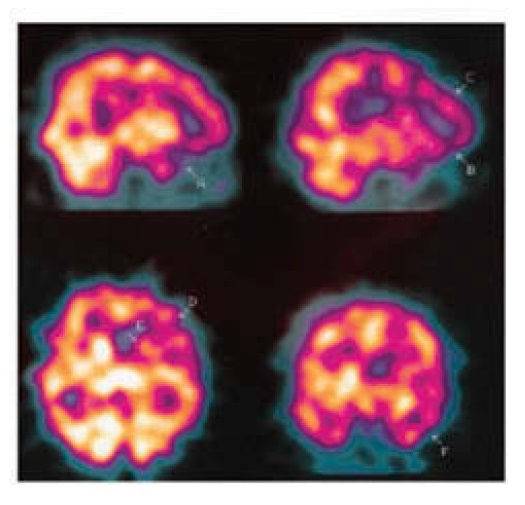

巴西一名49岁男性在中风过后性情大变,经诊断中风导致他患上了“病理性慷慨”。

他的主要症状是完全不顾及经济条件,大方的发钱,给街上的小孩发糖等等。

医生检查之后认为这名男性没有精神疾病或痴呆症状,他的超乎寻常并且持久的慷慨应该是来自中风的后遗症。

CT扫面显示他大脑的几个区域出现低血流量状况,包括前额叶。这些区域也许没有直接被中风损伤,但是在神经通路上与中风损伤的区域有所关联。由于这些改变可能导致了他性格的变化。

对于这种症状目前没有很好的治疗方案。

这个案例发表在2014年8月的Neurocase上。